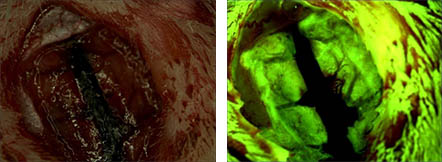

— 荧光 —

— FISH研究 —

荧光原位杂交技术(fluorescence in situ hybridization),简称FISH,是利用荧光标记的特异核酸探针与细胞内相应的靶DNA分子或RNA分子杂交,通过在荧光显微镜下观察荧光信号,来确定与特异探针杂交后被染色的细胞或细胞器的形态和分布,或者是结合了荧光探针的DNA区域或RNA分子在染色体或其他细胞器中的定位。